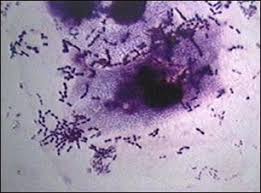

~ Tuberculosis ~

Es una infección contagiosa que compromete principalmente a los pulmones.

la produce la microbacterium tuberculosis.   Bacilo koch.Sintomas: